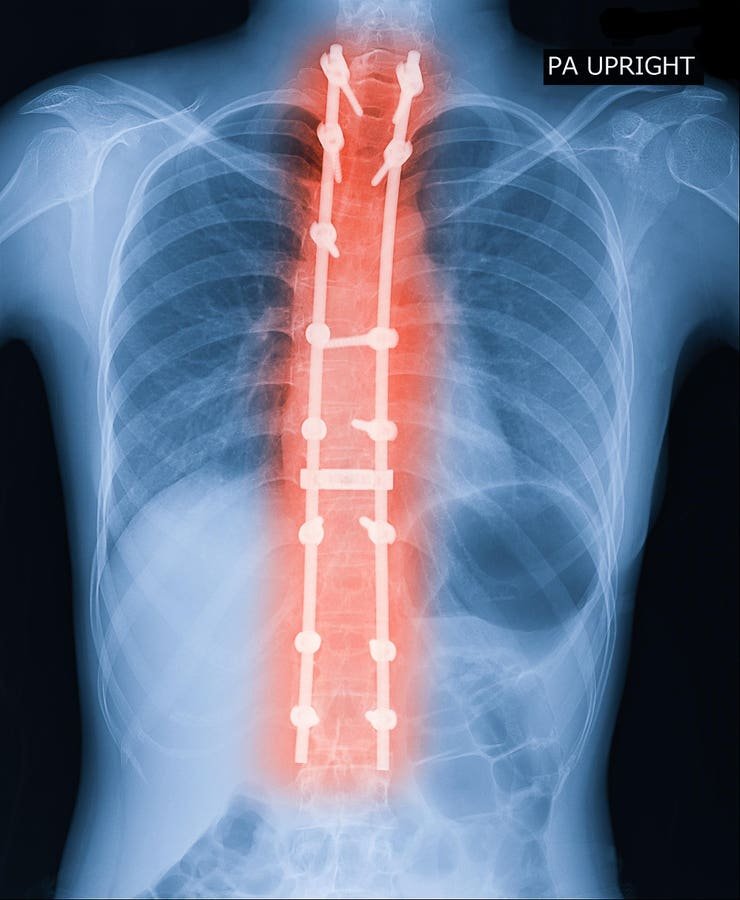

X-ray image of adult patient spine showing scoliosis surgery. Scoliosis surgeries are effective but expensive.

Adult symptomatic lumbar scoliosis (ASLS) poses a complex challenge in spinal care, profoundly impacting quality of life through pain, disability, and spinal deformity. This condition, characterized by lateral curvature in the lumbar spine of adults, differs from pediatric scoliosis. While pediatric scoliosis typically arises during growth, ASLS often results from degenerative changes in the lower back. Pain is a primary symptom in most adult cases, unlike the majority of pediatric cases. Additionally, because adult spines are less flexible, surgical interventions often require more invasive techniques, such as osteotomies or bone cuts, to achieve spinal alignment.